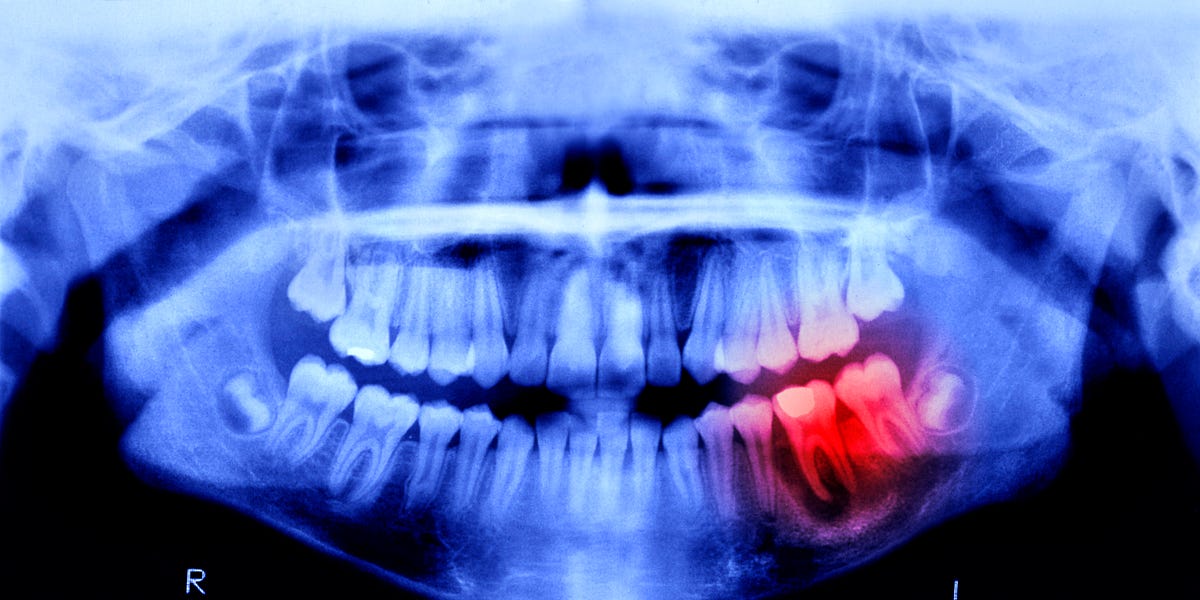

A tooth infection can easily spread to your brain and kill you. It’s a very short path.

doesnt need to spread to your brain, just cause sepsis lowering your blood pressure to dangerous levels, or to a major organ and kill you that way.

Gum disease has been linked to heart disease and now there might be a link to dementia due to the bacteria that can enter the bloodstream from the mouth.